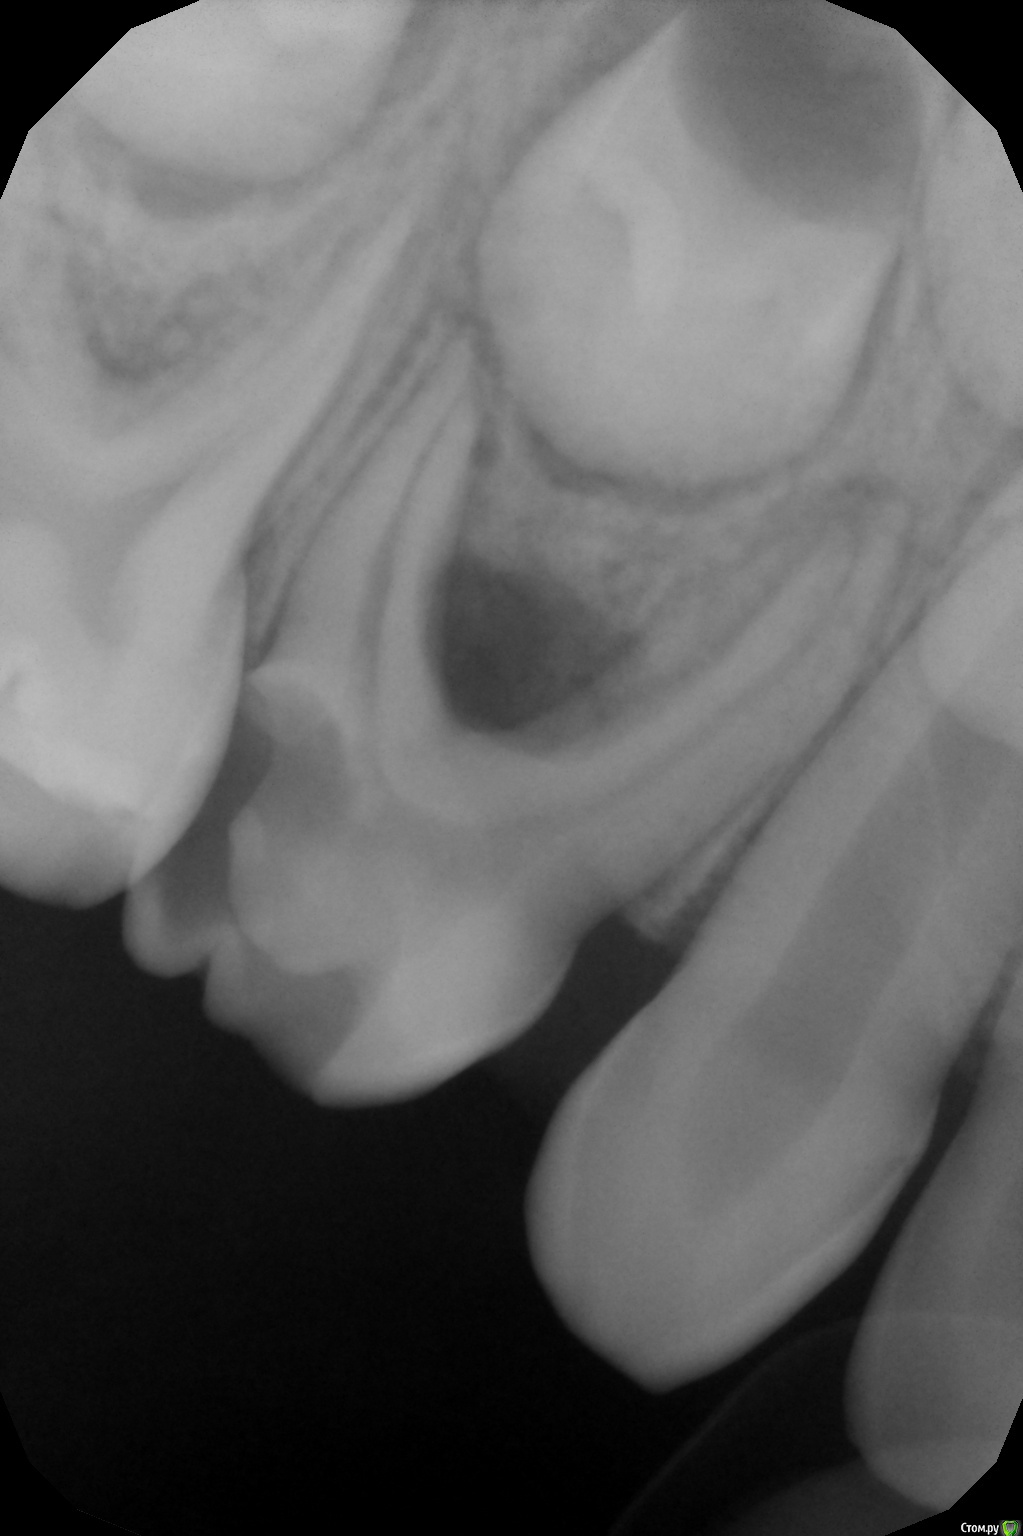

crown Опубликовано 31 мая, 2016 Поделиться Опубликовано 31 мая, 2016 5,5 лет, 75, ранее лечен по поводу кариеса, гигантская пломба, похоже на СИЦ, на десне с язычной стороны шишка), симптомы отсутствуют.Каналы про файлы 0.4 30, кровит нереально, особенно из дистальных, мед. обработка гипохлорит + перекись, оставил кальций на 2 недели. Сегодня свищ ушел, ничего не беспокоит, но дистальный язычный канал все равно кровит, остальные немного. Запломбировал метапексом вместе с кровью, назначил через пару дней. Почему кровит? И что делать с ним дальше? Удалять не хотят. Ссылка на комментарий

Джима Опубликовано 31 мая, 2016 Поделиться Опубликовано 31 мая, 2016 там же внутренняя резорпция обширная, в дистальных корнях. Надо было в дистальные не профайлами лезть, а вручную Н-файлами, и не "разрабатывать" ничего, а просто постараться выцарапать все грануляшки из каналов, не трогая сами стенки. возможно, что там уже дырки в стенках каналов были - тогда будет кровить, даже если в канале пусто. или вы дырки профайлом натёрли. или грануляции в каналах оставили. 2 Ссылка на комментарий

Kota Опубликовано 1 июня, 2016 Поделиться Опубликовано 1 июня, 2016 5,5 лет, 75, ранее лечен по поводу кариеса, гигантская пломба, похоже на СИЦ, на десне с язычной стороны шишка), симптомы отсутствуют.ИЛЬЯ_000.JPGКаналы про файлы 0.4 30, кровит нереально, особенно из дистальных, мед. обработка гипохлорит + перекись, оставил кальций на 2 недели. Сегодня свищ ушел, ничего не беспокоит, но дистальный язычный канал все равно кровит, остальные немного. Запломбировал метапексом вместе с кровью, назначил через пару дней. Почему кровит? И что делать с ним дальше? Удалять не хотят.ИЛЬЯ_я бы закрыла сейчас пломбой и ждала бы прорезывания 6 зуба. как только полностью прорежется шестерка- удалять и фиксатор места между 74 и 36. Ссылка на комментарий

crown Опубликовано 1 июня, 2016 Поделиться Опубликовано 1 июня, 2016 там же внутренняя резорпция обширная, в дистальных корнях. Надо было в дистальные не профайлами лезть, а вручную Н-файлами, и не "разрабатывать" ничего, а просто постараться выцарапать все грануляшки из каналов, не трогая сами стенки. возможно, что там уже дырки в стенках каналов были - тогда будет кровить, даже если в канале пусто. или вы дырки профайлом натёрли. или грануляции в каналах оставили.Думаете там 2 дистальных корня? Так то все верно, только резорбция в верхней трети корня, а дальше норм стеночки толстые, а кровит именно из апикальной части. Ссылка на комментарий

Джима Опубликовано 2 июня, 2016 Поделиться Опубликовано 2 июня, 2016 такая внутрянка потом вот так заканчивается:http://radikal.ru:8033/tempfiles/944645611b6245738098a3440436f518/-88693455.jpghttp://radikal.ru:8033/tempfiles/1f5a186b77424a42abc5b9ebf07dc18e/-88693455.jpgоставила тоже до прорезывания 4.6, там и коронки почти нет. Ссылка на комментарий

Джима Опубликовано 2 июня, 2016 Поделиться Опубликовано 2 июня, 2016 про ваш не знаю. там больно жидко метапекс в каналах выглядит, и кровило, говорите, сильно. вряд ли долго простоит. Света правильно написала, 36 выйдет - и на выход. Ещё раз напишу. Верхушечной резорбции в чистом виде у молочек практически не бывает. Резорбция идёт по фуркации с переходом на малую кривизну и до апекса - организм пытается съесть всё, что содержит воспалённую пульпу. Даже ещё не так: воспалённая пульпа, в т.ч. и в мелких канальцах в указанной зоне, работает как одно целое с воспалённым периодонтом в этой зоне. Вместе они съедают малую кривизну (забавно, что часто целым остаётся собственно апекс, бывает, что он полностью отделяется от корня). Наружная часть корня остаётся целой. А корневой канал становится срезанным по косой, с широченным выходным отверстием (назвать это апексом сложно). Чем больше эта дыра, тем быстрее вымывается материал из корневого канала. А пустоты в природе не бывает Мы используем активные силлеры - гидроокись кальция или ЦОЭ. Они не дают размножиться флоре. Нет силлера - есть флора, потому что говорить о 100% герметичных реставрациях в детстве не приходится: зубки мелкие, насыщенные органикой и одновременно хрупкие, с очень тонкими стенками. Поэтому наше лечение - это балансирование между плохими микробами в плохом зубе и хорошо проделанной работой в хорошем здоровом детском организме. Чем плотнее забита устьевая половина корня и чем надёжнее реставрация - тем выше шансы на успех у здорового ребёнка. 1 Ссылка на комментарий